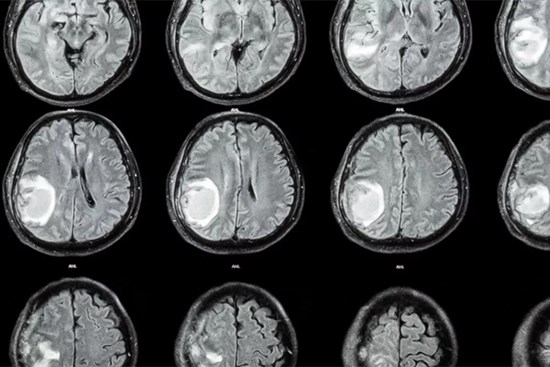

Đầu bé 1 tuổi tự nhiên to lên, bác sĩ lấy ra cả một bào thai trong não

Ca bệnh đặc biệt được công bố trên tạp chí Neurology được xác nhận là một trường hợp thai trong thai cực hiếm, trong đó đứa bé ra đời đã mang theo bào thai người em song sinh trong não.